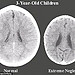

儿童大脑扫描图揭示疏于照管与用心养育的区别

儿童大脑扫描图